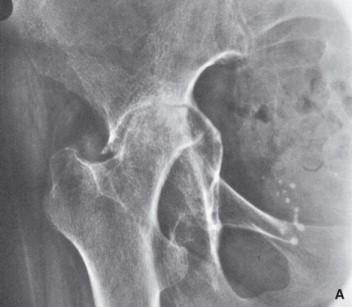

- Artroplastia de reemplazo total de cadera: Esta cirugía es comúnmente recomendada para pacientes mayores con artritis reumatoide avanzada que han experimentado un deterioro significativo en la movilidad y el funcionamiento de la cadera.

| Artroplastia de reemplazo total de cadera | Mejora la movilidad y calidad de vida del paciente. | Requiere de un tiempo de recuperación prolongado. |